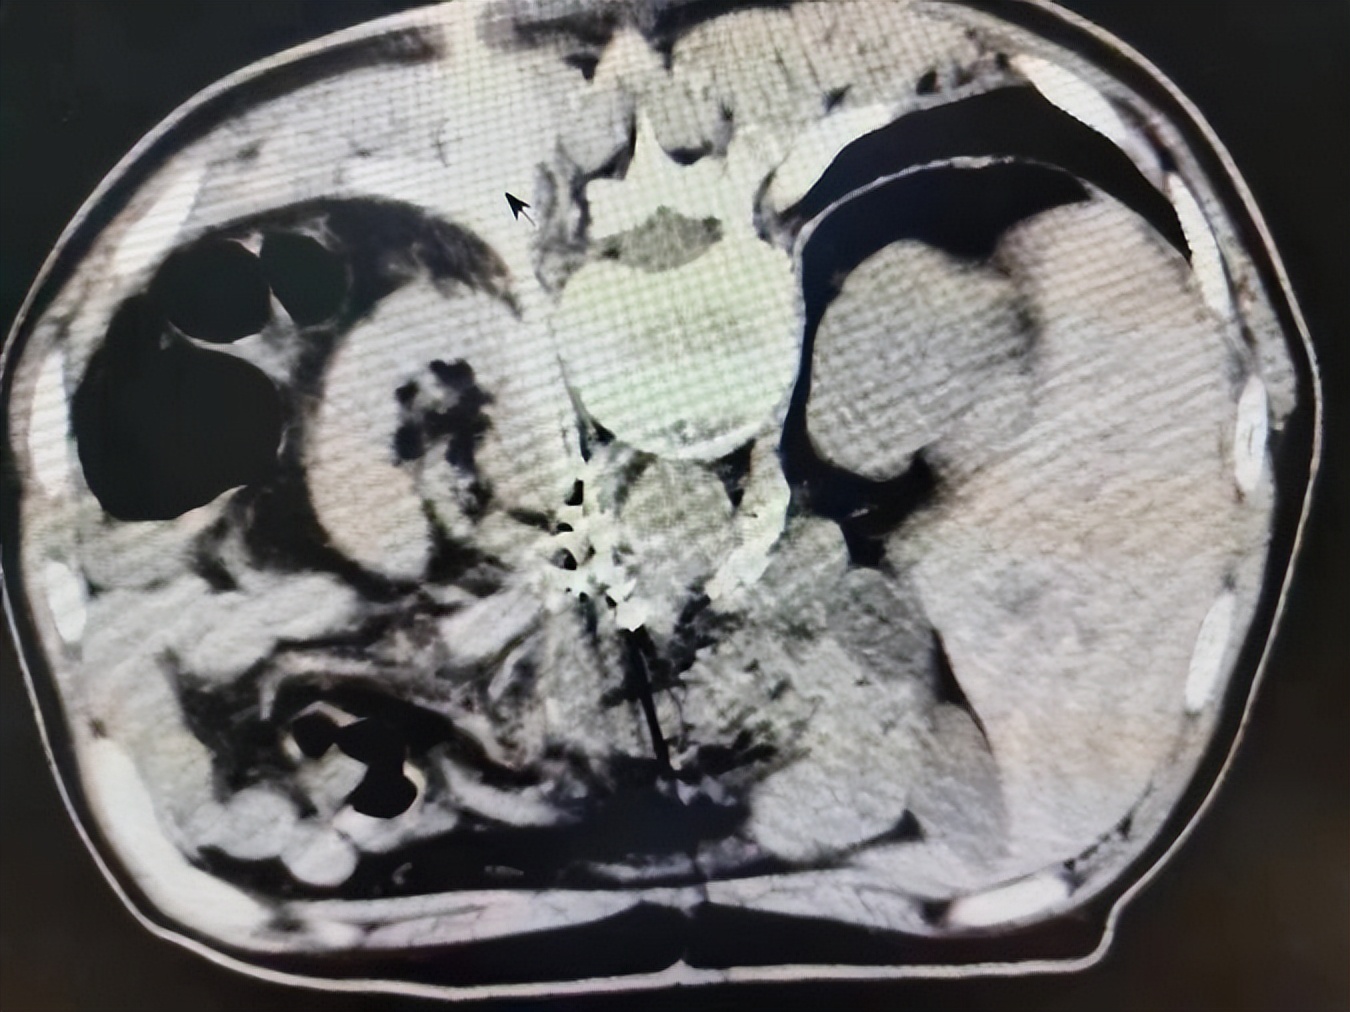

CT引导下穿刺定位

CT引导下粒子植入